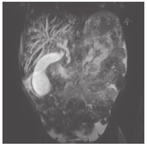

患儿,男,4岁,因"间断腹泻0.5年,皮肤、巩膜黄染5 d"于2017年3月11日就诊于复旦大学附属儿科医院。患儿0.5年前开始反复出现油腻饮食后腹泻,为稀糊便,1~2次/d,无黏液脓血,无发热、腹痛、皮肤黄染,可自行缓解。曾予中成药调理,无明显改善。入院前5 d因体检发现贫血后口服铁剂治疗,渐出现皮肤、巩膜黄染,无发热,不伴腹痛、腹泻及大便颜色变浅,无皮肤瘙痒,无纳差、乏力、恶心、呕吐,小便深黄。发病后曾到当地医院住院治疗2 d,检查发现肝功能异常,贫血、白蛋白低下、凝血功能异常、IgG低下,为进一步诊治,转至复旦大学附属儿科医院。患儿系第1胎,第1产,足月顺产,出生体质量3 650 g,无窒息及抢救史。患儿出生后母乳喂养,按时添加辅食。运动及智力发育与同龄儿相仿;出生后接种卡疫苗后出现左腋下淋巴结脓肿;婴儿期曾2次患重症肺炎并行机械通气。父母体健,非近亲结婚,无明确家族性、遗传性疾病史。体格检查:体质量13 kg,身高95 cm。贫血貌。颈部及腋下可触及黄豆大小淋巴结,皮肤及巩膜中度黄染,无肝掌、蜘蛛痣。心肺查体无特殊,肝脏肋下3 cm,剑突下3 cm,质韧,脾脏肋下未触及。主要实验室检查:血常规白细胞18.4×109/L,嗜酸性粒细胞0.188,血红蛋白84.2 g/L,中性粒细胞0.105,血小板557×109/L,网织红细胞0.064,C反应蛋白64 mg/L;血生化:白蛋白23.9 g/L,碱性磷酸酶171 IU/L,丙氨酸转氨酶132 IU/L,天冬氨酸转氨酶199 IU/L,磷酸肌酸激酶1 710 IU/L,肌酸激酶105 U/L,肌酸激酶同工酶105 IU/L,结合胆红素93.2 μmol/L,γ-谷氨酰转移酶673 IU/L,球蛋白14.7 g/L;钾4.3 mmol/L,乳酸脱氢酶571 IU/L,血氨78 μmol/L;Coomb′s试验阴性;血甲胎蛋白、癌胚抗原、铁蛋白、神经元特异性烯醇化酶均正常;血IgA 0.44 g/L,IgG 2.40 g/L,IgM 0.97 g/L;总IgE 10.0 kU/L;CH50正常,补体C3、C4正常;流式细胞检测CD系列未见明显异常,活化淋巴细胞正常;结核菌T细胞斑点检测(T-SPOT)阴性,血寄生虫抗体阴性,大便常规、隐血及寄生虫检查均未见异常;支气管镜肺泡灌洗液:抗酸杆菌阴性,灌洗液半乳甘露聚糖(GM)试验阴性;腹部磁共振成像(MRI)、磁共振胰胆管成像(MRCP)示肝内胆管、肝总管、胆囊及胆总管扩张(图1);胸部CT示两肺多发斑片、条索状高密度影,局部与邻近胸膜黏连,局部支气管管腔扩张。胸腔见少量积液。骨X线片:双下肢诸骨骨质稀疏(图2);肝脏病理:肝细胞肿胀,部分气球样变,部分肝细胞胞质内见小空泡形成,少量肝细胞内胆汁淤积;部分肝血窦轻度扩张,枯否细胞轻度增生;汇管区纤维组织增生,胆小管增生,部分大胆管周围纤维组织增生,较多嗜酸性粒细胞及少量淋巴细胞、中性粒细胞浸润(图3)。胃镜及小肠胶囊内镜提示浅表性胃炎(轻度),小肠黏膜炎;胃窦黏膜病理活检:轻度慢性炎症,幽门螺杆菌(-)。骨髓涂片未见明显异常。入院后积极给予无脂且蛋白以植物蛋白为主饮食,头孢曲松抗感染,静脉丙种球蛋白、白蛋白、补充脂溶性维生素支持治疗,熊去氧胆酸利胆,患儿腹泻、胆汁淤积好转。获得患儿监护人知情同意后对患儿家系进行高通量测序发现,患儿CD40LG基因突变(exon5 c.506A>G,p.Y169C),169位氨基酸有酪氨酸变为半胱氨酸,为致病性突变(rs786205606),母亲为携带者,为已知X连锁隐性遗传性疾病致病性基因突变。